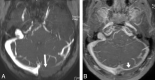

Fig 5.

Forty-three-year-old man who underwent MR and MRV investigation for posterior fossa hemorrhage. Axial thick-slab MIP reformations of 2D TOF (A) and static part of combo-4D MRV (contrast-enhanced 3D VIBE, B) are targeted on lateral sinuses (slab thickness, 20 mm). On TOF MRV image, large flow gap in proximal transverse sinus is demonstrated (long white arrow in A). Combo-4D MRV image shows hypoplastic transverse sinus without evidence of thrombosis (short white arrow in B).